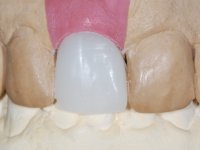

After performing an impression of the implant and making the models, we tested several rehabilitative options with the help of the implant brand planning kit. None proved capable. In this sense and as a resource solution, an innovative solution was proposed. It was proposed to make a milled Zr abutment with an appropriate design to receive a veneer that would hide the screw access hole. The veneer itself had a ceramic-coated Zr infrastructure. The goal was to achieve retention and strength by screwing the abutment and aesthetically solve the case with the veneer.

After the impression of the implant using a double-mix technique with double viscosity and the collection of shape and color information by the ceramist, we proceed with the work. In the model, a syn octa was placed over the implant, and a screw was placed on it to assess its emergence in relation to the incisal edge. Then, an adequate emergence profile in the artificial gingiva was prepared. A abutment with characteristics suitable for overbite and simultaneously capable of receiving a veneer was waxed on top of this scenario. This waxing gave rise to the manual milling of a very personalized abutment. An infrastructure in Zr was also made for the veneer with a very great adaptation to the abutment. On this infrastructure ceramics were placed. Ceramic fluorescence sought to compensate for the lack of fluorescence that Zr had and obviously further customize the aesthetics. The adhesive bridge was removed and the definitive work was placed. The syn octa was initially tightened with 35 N to the implant and then the Zr abutment was tightened over the syn octa with 15 N. The access hole was plugged and then the veneer was cemented with resin-reinforced glass ionomer. After 15 years, the patient returned to the consultation with tooth mobility. Fortunately, nowadays we have the possibility of having dynamic tightening wrenches that allow tightening screws with greater inclinations. An access cavity was made without damaging the incisal edge of the veneer. Tightening was done with a dynamic wrench with 15 N torque. The hole was covered with Teflon and filled with composite resin. This solution allowed the problem to be solved in a simple and economical way.